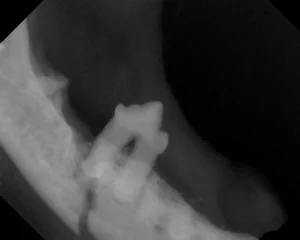

A mandibular fracture is seen on the x-ray above.